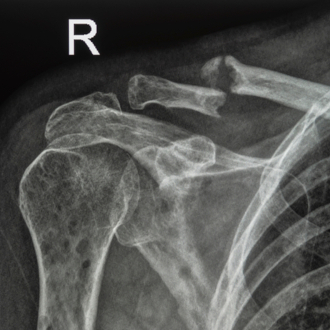

Диагностика синостоза включает в себя несколько этапов, начиная с осмотра врача и заканчивая инструментальными исследованиями. Во время осмотра врач обращает внимание на внешний вид и форму головы ребенка, а также на наличие асимметрии лица, глаз и ушей. Он также оценивает движение шейного позвонка и пытается определить наличие естественных швов и швов, которые могут быть покрыты коростой.

- Рентгеновское исследование головы и черепа. Рентгеновский метод может использоваться для оценки костей головы, включая швы и швы. Однако это исследование может быть менее информативным в сравнении с КТ и МРТ.